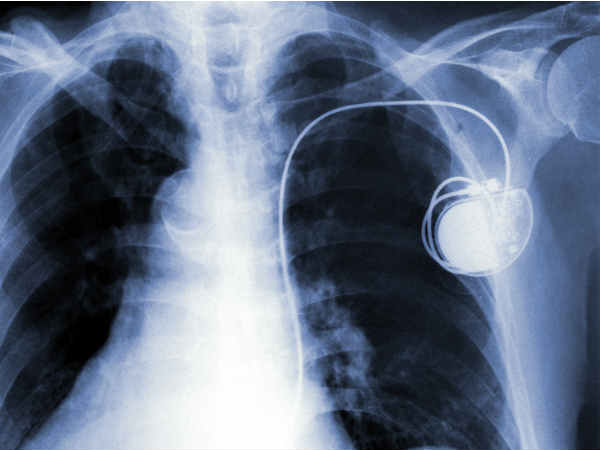

పేస్ మేకర్స్ గురించి మీరు తెలుసుకోవల్సిన కొన్ని విషయాలు

పేస్ మేకర్ 25 నుండి 35 గ్రాముల బరువున్న ఒక చిన్న కృత్రిమ పరికరం, దీనిని గుండె రేటు తక్కువగా ఉన్న రోగులకు కండరాలకు విద్యుత్ ప్రేరణ చేసి గుండె కొట్టుకోవడానికి ఏర్పాటు చేసే కృత్రిమ పరికరంగా దీనిని ఉపయోగిస్తారు.

పేస్ మేకర్ ని చర్మం కింద ఉన్న ఎడమ లేదా కుడి మెడ ఎముక, కొవ్వు కణజాలం క్రింద అమరుస్తారు. లీడ్స్ సిరాల ద్వారా పంపబడి, ఒక మూల గుండె కండరాలకు కలుపబడి, మరోవైపు పేస్ మేకర్ కి కలుపబడి ఉంటాయి. పేస్ మేకర్ పారామీటర్లు ప్రోగ్రాం చేయబడి ఉంటాయి, ఆ ప్రోగ్రామర్ ని బైట నుండి మార్చవచ్చు. సాధారణంగా ఒక పేస్ మేకర్ కరెంట్ మీద ఆధారపడి గుండె ఉద్దేపనాన్ని ఉపయోగించుకుని 10 నుండి 12 సంవత్సరాల పాటు పనిచేస్తుంది.